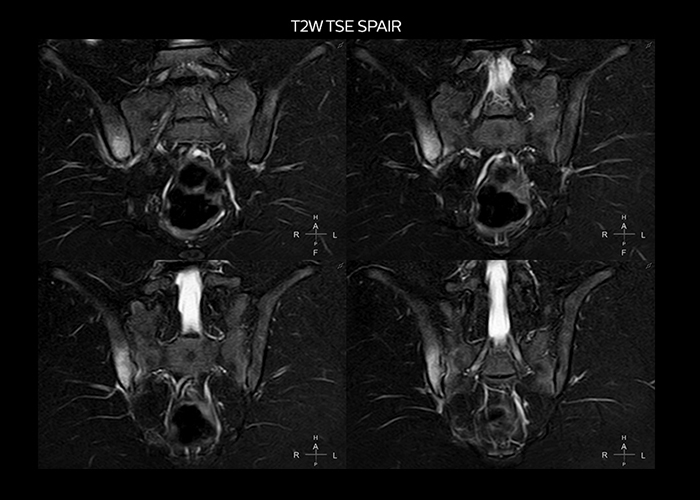

“To avoid coil changes we plan examinations of similar anatomies back to back, such as head and spine. Multiva helps us here a lot because coils don’t need to be changed frequently. Moreover, thanks to parallel imaging technology and 16-channel HeadSpineTorso and 8-channel MSK coils we are able to achieve excellent image quality. In this way Multiva helped us to increase both image quality and productivity.”

“Neurological cases, such as brain and spine imaging, represent the largest share in our MR scanning, followed by musculoskeletal cases. In general, we use simple and basic imaging protocols. But occasionally, we use advanced techniques for problematic cases if necessary.

“Most important, Multiva satisfies our clinical imaging needs very well,” says Mr. Tuna. “Many features of Multiva have become similar to the Ingenia system. Even in more complex imaging such as abdominal and cardiac, the image quality and performance of Multiva is better than we expected. General surgeons and physicians from our hospital’s internal medicine department prefer to refer to us because of this.”